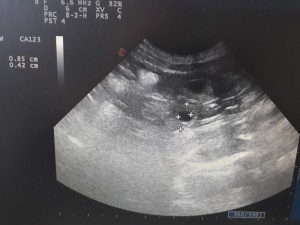

7.7. Čekáme 6 štěňátek

Přesně 30. den gravidity jsem zopakovala sono a Kety má v bříšku 6 malých štěkátek. Bytečky pro štěňátka jsou skoro 3 cm velké a v nich plavou už skoro 1cm velcí červíčci, u kterých už jsou rozeznatelné jednotlivé části těla a bijící srdíčka. Tak hlavně, aby to nadále bylo bez problémů.